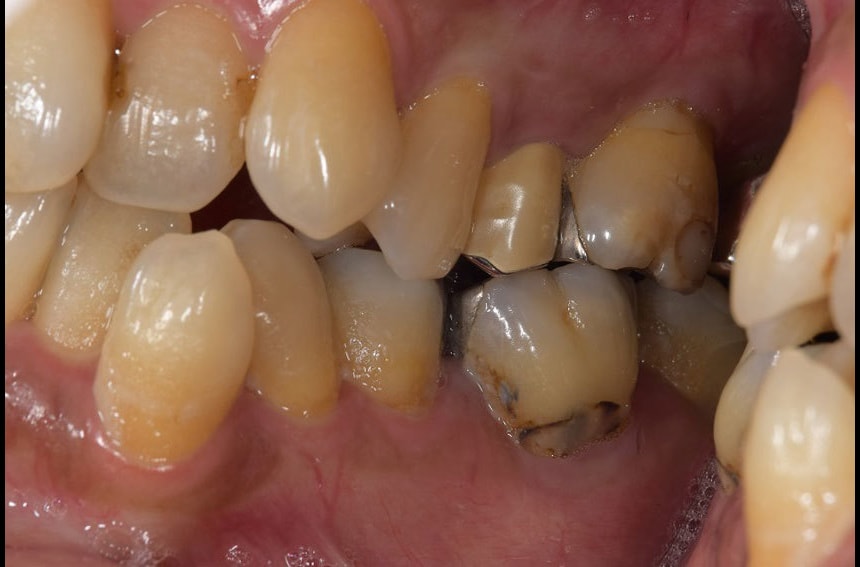

右奥歯の治療前後

左奥歯の治療前後